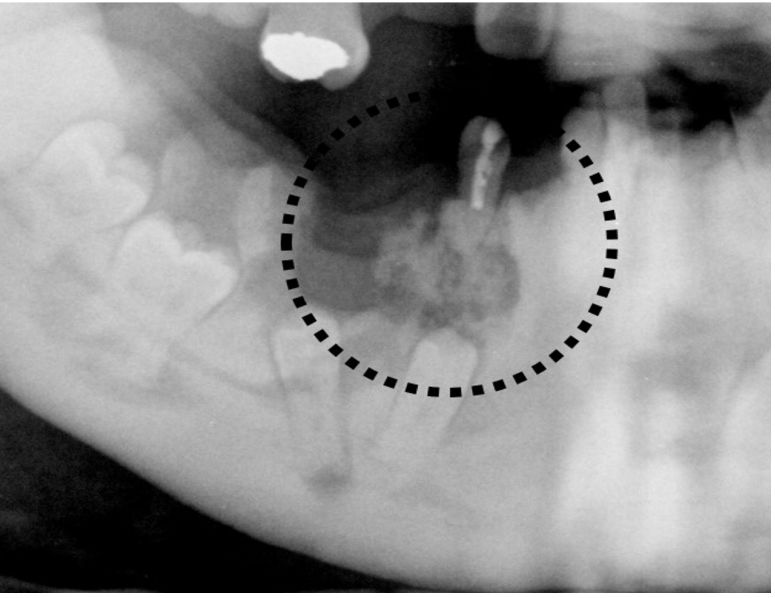

67.45歲男性因下顎右側有一個無疼痛的腫脹而來求診,經影像檢查如附圖所示,右上小圖是左大圖虛線位置的 斷層圖,經切片後病理診斷為纖維骨性病變,結合影像的發現,此病患最可能罹患下列何種疾病?(A)繁盛性牙骨質骨發育不良(florid cemento-osseous dysplasia)(B)局部牙骨質骨發育不良(focal cemento-osseous dysplasia)(C)根尖周圍牙骨質骨發育不良(periapical cemento-osseous dysplasia)(D)骨化纖維瘤(ossifying fibroma)